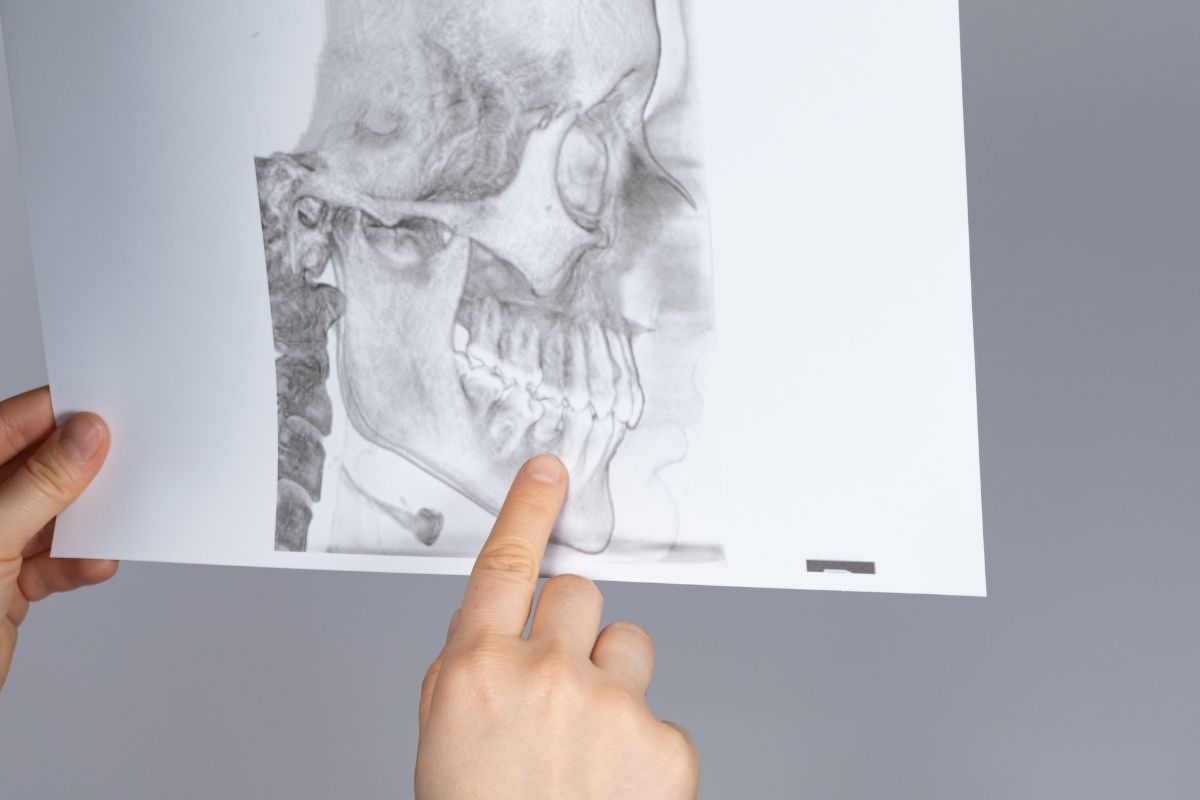

La articulación temporomandibular (ATM) es la articulación más compleja de nuestro cuerpo. Se encarga de conectar la mandíbula y el cráneo y es utilizada por el ser humano para funciones esenciales como masticar, hablar, tragar y bostezar. ¿Sabías que más de un 30% de la población padece una disfunción de la ATM y no es consciente de ello?

Diagnóstico de la ATM:

Un diagnóstico preciso es fundamental para el desarrollo de un plan de tratamiento efectivo para los trastornos de la ATM. Esto puede implicar una evaluación clínica completa, pruebas de imagen y, en algunos casos, pruebas de laboratorio.

La evaluación clínica incluirá un examen detallado de la mandíbula, la cabeza, el cuello y la cara, evaluando la amplitud de movimiento, la presencia de dolor o sensibilidad, y los sonidos asociados con el movimiento de la mandíbula.